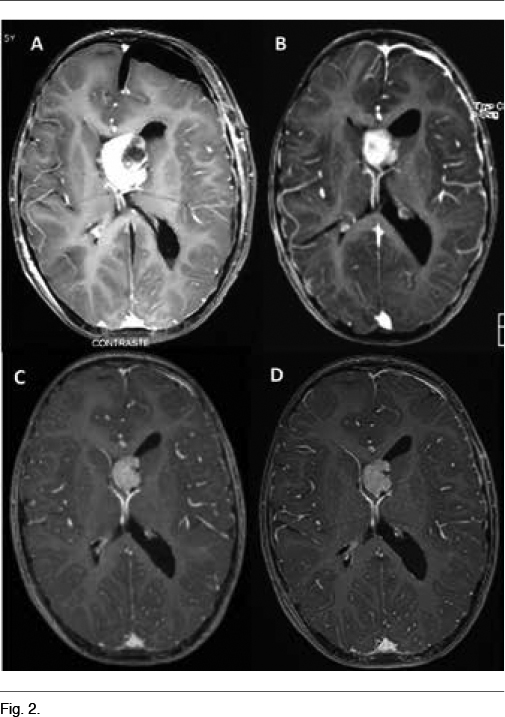

A los 5 años instala un síndrome de hipertensión endocraneana dado por cefaleas que progresan en el correr de tres meses, llegando los días previos a la consulta a despertarlo en la noche y a acompañarse de vómitos matinales que alivian las cefaleas. La tomografía computada de cráneo de urgencia informa un proceso expansivo de tercer ventrículo, que obstruye el agujero de Monro, determinando una hidrocefalia supratentorial de ambos ventrículos laterales, mayor a izquierda, con desviación de línea media a derecha de 12mm, edema transependimario e intensa captación de contraste (Figura 1). Con planteo de hidrocefalia secundaria a SEGA, se realiza en una primera instancia una derivación ventrículo-peritoneal de urgencia a nivel del ventrículo lateral derecho, para tratamiento de su hipertensión endocraneana descompensada. El procedimiento no presenta complicaciones, quedando el paciente asintomático luego del mismo. En el fondo de ojo post-derivación se observa edema de papila bilateral. La RM post-operatoria muestra el SEGA y la persistencia de una hidrocefalia a nivel del ventrículo lateral izquierdo. En una segunda instancia se realiza la cirugía del tumor lográndose una resección parcial del mismo, con un remanente tumoral de 14.3cm3 (Figura 2A) La anatomía patológica confirmó el diagnóstico de SEGA.

Se decide iniciar everolimus, a pesar que su indicación como tratamiento adyuvante es off-label (11). Se inició everolimus a 2.5mg/día (3mg/m2/día) aumentándose la dosis a 5 mg/día por presentar dosificación sérica de 1.5ng/ml, por debajo del rango terapéutico (3-15ng/ml), lográndose una concentración de 9.4ng/ml. En las RM de control se evidenció una reducción del tamaño tumoral del 54.5% al mes (6.5cm3) (Figura 2B), del 65.5% a los 3 meses (4.9cm3) (Figura 2C) y del 68.5% a los 6 meses (4.5cm3) (Figura 2D). Como efectos secundarios presentó astenia al inicio del tratamiento, aftas bucales que no interfirieron con la alimentación ni requirieron tratamiento y 3 episodios de infección respiratoria alta que fueron bien toleradas y no requirieron modificaciones en la medicación. Los controles paraclínicos no evidenciaron alteración en la función renal, perfil lipídico, glicemia, ionograma, funcional y enzimograma hepático, en el hemograma ni en la orina.